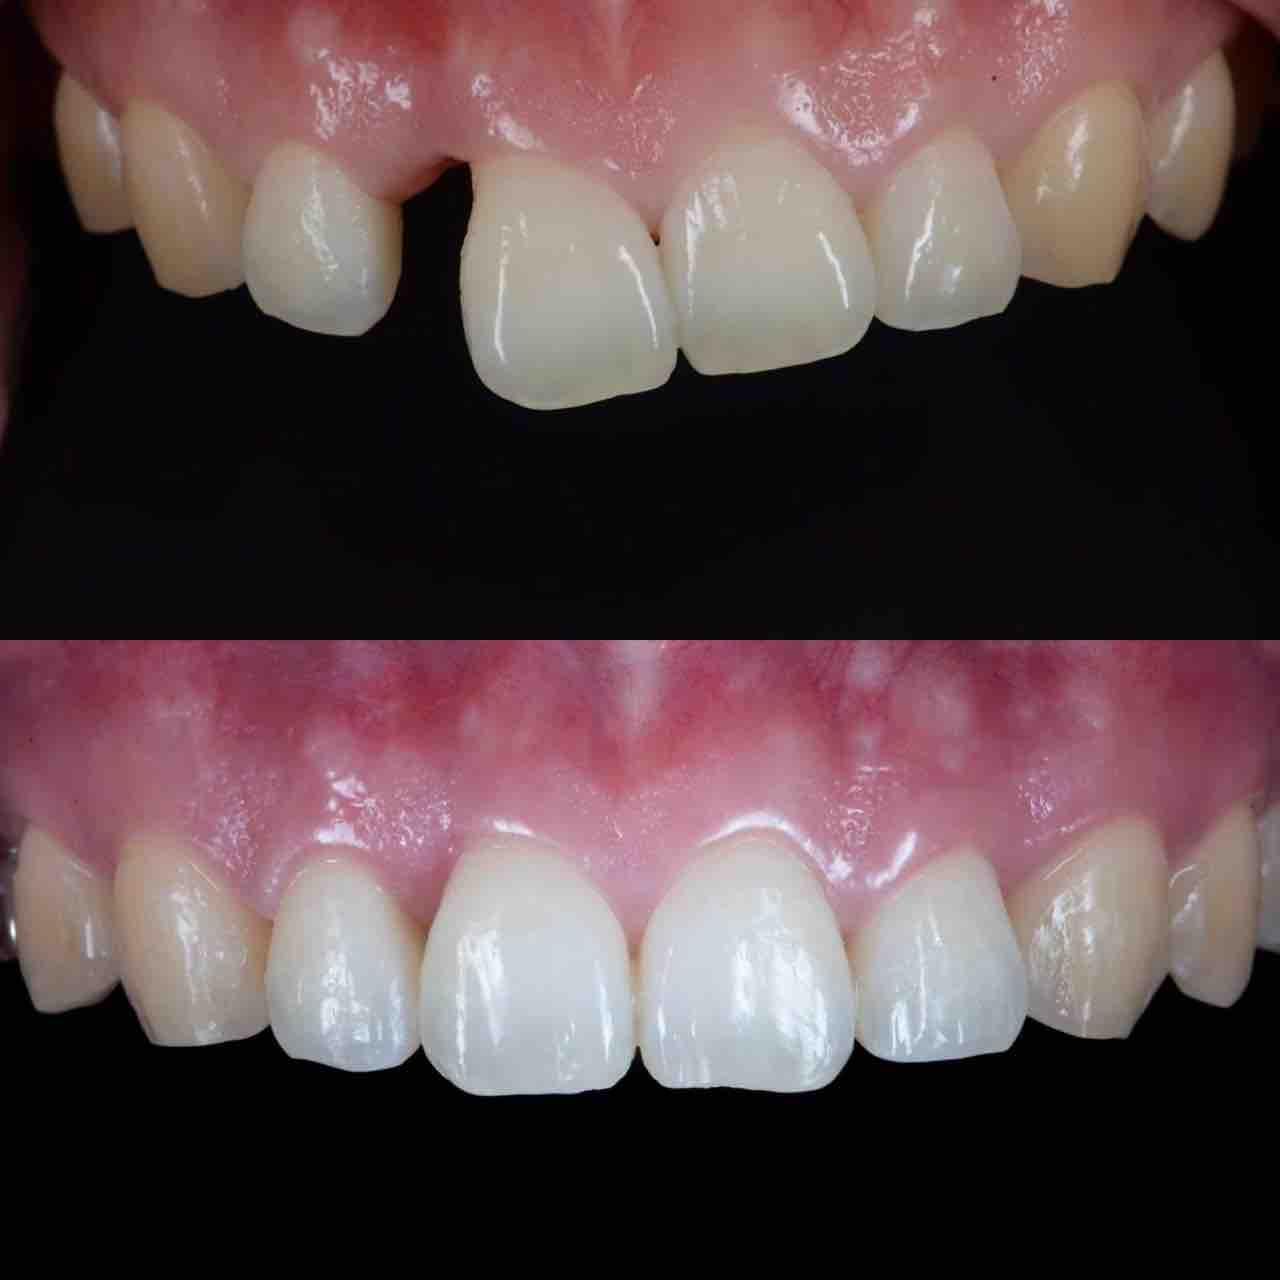

¥¤¥ó¥¹¥¿¥°¥é¥à¤ËºÜ¤»¤Æ¤¤¤ëÅö±¡¤Î¾ÉÎã¤Ç¤¹